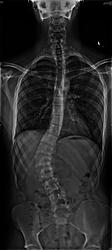

Hey guys, I don't post much here that much, some of you may not remember me or even know me. I have been very busy for the past few months with school and with my back. I have been dealing with scoliosis for over a year and a half now. And It turns out I first caught it after my growth spurt when I was 18. I had an x-ray and it was "supposedly" 15 degrees by stupid doctor number 1. It wasn't actually 15 degrees, it was 40 degrees and by 09, it had gone to 53*. Now my only option is a spinal fusion. It's really a big problem for me, it causes daily pain. I am having surgery Monday, December 28, 2009. I would just really like it if you guys wished me luck and kept me in your prayers so I have a safe surgery and have no problems. Thanks.

Here are some X-rays to show you how my spine looks.